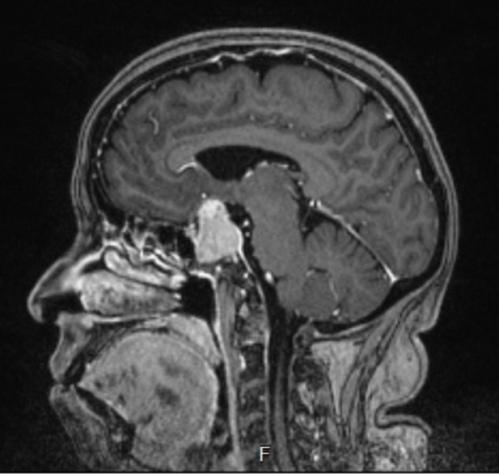

● Hernia de disco

● Tumores cerebrales, de médula espinal y columna vertebral.

● Cervicalgia, lumbalgia, ciatalgia

● Mielopatías

● Radiculopatía

Especialistaencirugíade columnavertebral

● Adenoma de hipófisis

● Aneurisma cerebral

● Traumatismo craneoencefálico

● Fracturas craneales

● Hemorragias cerebrales

● Hidrocefalia

● Neuralgia del trigémino

Consultorio 612

Ced. Prof. 3222781 Ced. Esp. 5088034

Consultorio 318

dr_rogerperez@yahoo.com.mx www.neurocirujanoenmerida.weebly.com

Citas al 999 270 6513

Dr.RogerPérezCastillo NEUROCIRUGÍA

• TUMOR CEREBRAL EN NIÑOS

• TUMOR CEREBRAL EN ADULTOS

• HIDROCEFALIA

Cédula Profesional: 2659973 Cédula Especialidad: 4896511

• MICROCIRUGÍA DE LA HIPÓFISIS Y REGIÓN SELAR

• MICROCIRUGÍA DE HERNIA DE DISCO

• CIRUGÍA DE TUMORES CEREBRALES

• CIRUGÍA DE HERNIA DISCAL CERVICAL

• CIRUGÍA DE LESIONES CEREBRALES

• BIOPSIA DE NERVIOS PERIFÉRICOS

• BIOPSIA CEREBRAL

Dentro de la plaza UpTown

• ENFERMEDAD CEREBROVASCULAR

• HEMORRAGIA CEREBRAL

• DERRAME CEREBRAL

• DISCO ROTO

• CIÁTICA

• ANEURISMA CEREBRAL

• ADENOMA SECRETANTE

Urgencias: 9999 47 2495 Hospital Faro: 9999 21 4962 Star Médica: 9999 43 3334 Consultorio 417 DR.LUISALBERTO RAMÍREZLÓPEZ CirugíaNeurológica,Cirugía

www.neurocirujanodrramirez.com HospitalFarodelMayab Consultorio 711

Cerebrovascular, Cirugía

ColumnaVertebral.